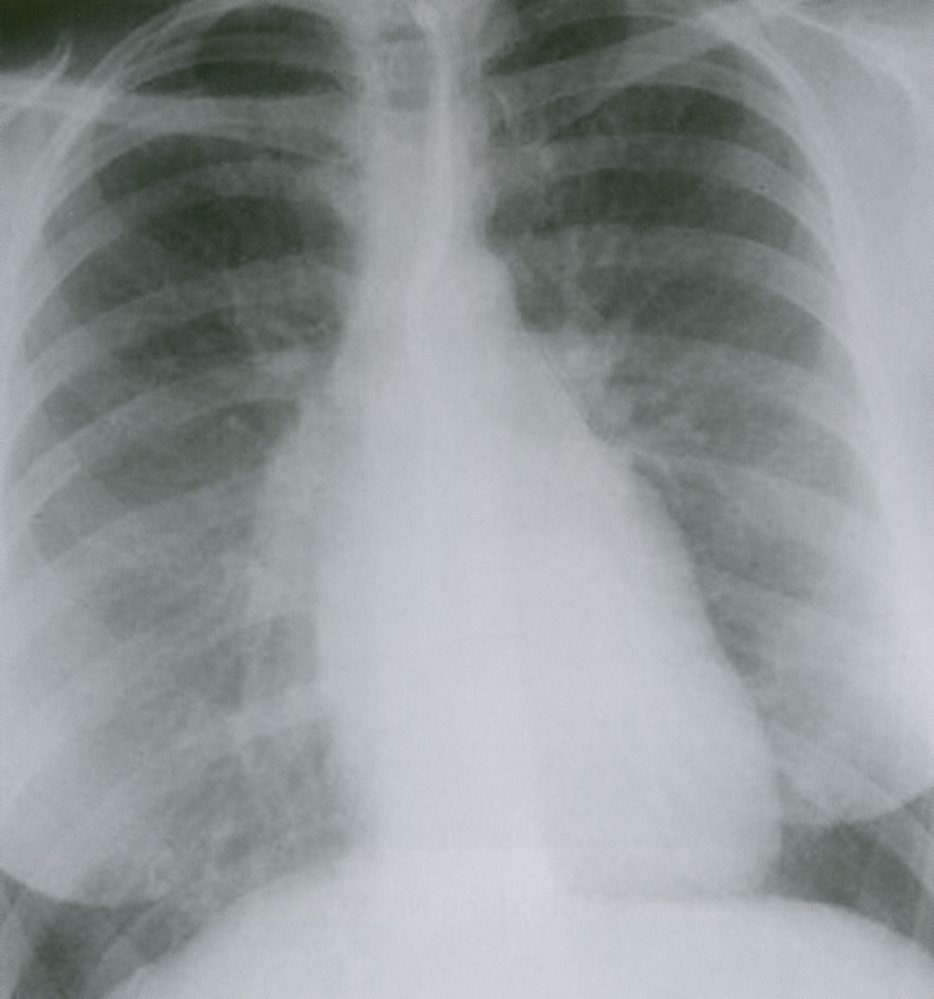

Chest x-ray [3]

• Enlarged left atrium

• Enlarged left ventricle

• X-ray findings of pulmonary edema